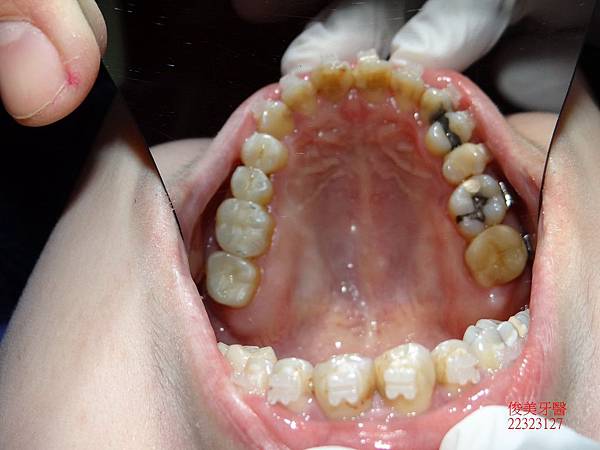

牙齒排列不整。

牙縫蛀牙。

上排牙齒已有延長的現象,牙縫更容易塞東西,且沒有咀嚼功能。

蛀牙過多,且深。牙弓形狀已非標準形態。